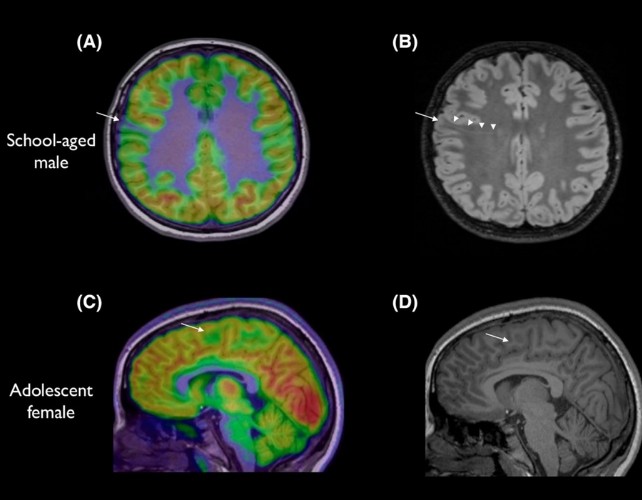

Uma nova ferramenta de inteligência artificial pode detectar alterações minúsculas no cérebro de crianças com epilepsia, abrindo caminho para cirurgias que mudam vidas. A epilepsia tem várias causas e, em torno de 30% dos casos, decorre de alterações estruturais no cérebro; essas lesões pequenas costumam passar despercebidas pelo MRI, especialmente quando estão nas dobras do cérebro. Em estudo liderado pela neurologista pediátrica Emma Macdonald-Laurs, a IA foi treinada em imagens de cérebros infantis para localizar lesões do tamanho de um mirtilo ou menores. Ela não substitui radiologistas nem médicos de epilepsia, mas funciona como um detetive que junta as peças do quebra-cabeça com mais rapidez, permitindo oferecer cirurgias potencialmente salvadoras.

A equipe treinou uma IA para ler imagens cerebrais de crianças e encontrar lesões do tamanho de um mirtilo ou menor. Quando a IA analisou imagens de MRI combinadas com PET, a taxa de detecção foi de 94% em um grupo de teste e 91% em outro. No primeiro grupo, 12 de 17 crianças foram operadas para remover as lesões, e 11 ficaram sem crises. A pesquisadora Emma Macdonald-Laurs afirmou que “o detector não substitui radiologistas ou médicos, mas é como um detetive que nos ajuda a montar o quebra-cabeça mais rapidamente, abrindo caminho para uma cirurgia potencialmente salvadora.”